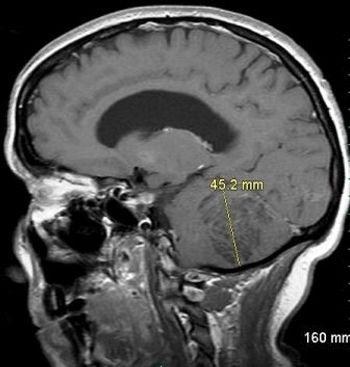

Neurofibromatosis, neuroretinitis, neurologic complications of Down syndrome, Lhermitte-Duclos disease, neurosarcoidosis-find insights here for defeating nervous system disorders.